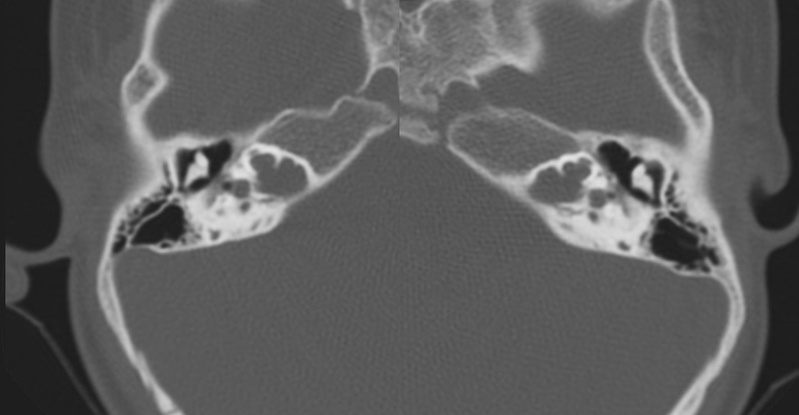

Evaluación de Imagen (TC)

Los hallazgos radiológicos, mediante TC de oídos a cuatro pacientes varones y una madre oyente, portadora obligada, se analizaron y clasificaron según Sennanoğlu et al. [8,9]. En ese sentido, son consistentes con PI-III en tres de ellos: IV-1, IV -2 y IV- 4. El paciente IV-3 mostró PI-I; la madre portadora obligada no mostró alteración alguna (Ver Tabla 3). En los cuatro pacientes estudiados de esta familia observamos dos tipos de MOI, PI-I y PI-III, incluso entre los hermanos IV-2 y IV-3, que presentaron diferente tipo de PI, lo que evidencia expresividad variable. La malformación PI-III es de las MOI menos frecuente y se encuentra presente en este estudio familiar como predominante.

Imagen 7

Corte axial de TC de ambos oídos del paciente IV-1 con PI tipo III.